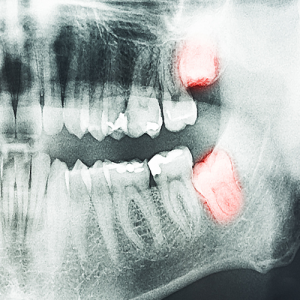

کشیدن به موقع دندان عقل

برداشتن و کشیدن به موقع دندان عقل یک روش کاملاً طبیعی است. اگر دندانپزشک به شما بگوید که نیاز به برداشتن دندان های عقل دارید ، اصلا جای نگرانی ندارد و برداشتن دندان های عقل